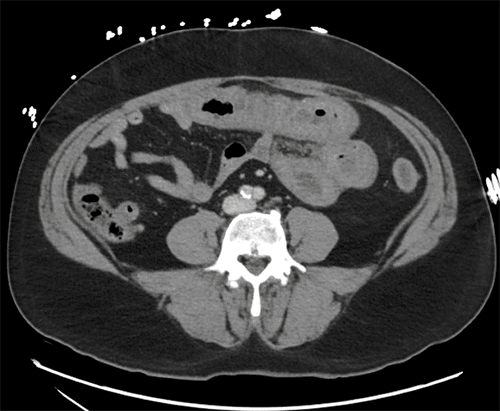

In the emergency department, a computed tomography (CT) scan of the abdomen and pelvis with intravenous contrast was obtained. The imaging revealed significant circumferential thickening of multiple small bowel loops with associated adjacent mesenteric edema and distal small bowel decompression. These findings were highly concerning for a closed-loop small bowel obstruction (Figure 2).

Figure 2. CT Findings of Small Bowel Vasculitis. Published with Permission

Contrast-enhanced CT scans of the abdomen. The images demonstrate diffuse, circumferential wall thickening of multiple small bowel loops accompanied by adjacent mesenteric edema and inflammatory stranding. Decompressed distal small bowel segments are also noted, features which, in this clinical context, were attributed to severe enteric vasculitis rather than mechanical obstruction